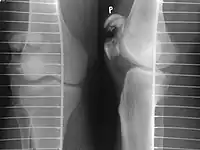

Other namesBroken kneecap

A fracture of the patella seen on a lateral view